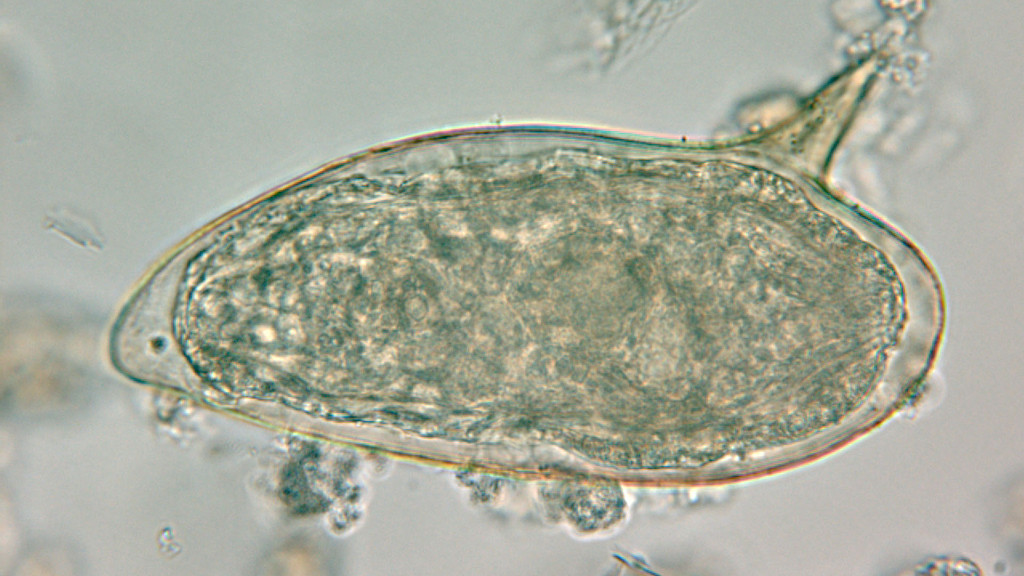

Шистосомоз: что нужно знать о паразитах